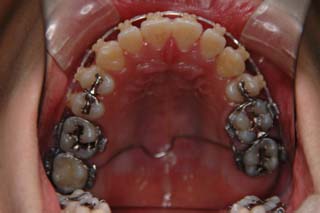

マルチブラケット装置でまっすぐに並べただけの状態です。なるほど、まるで噛めてない状態なのがよく分かります。ここでよく有りがちな矯正治療だと、上の前歯と下の前歯にゴムを1日中かけて噛ませていくのですが、それでは以前と同じく、関節をずらして噛むだけの人になってしまうでしょう。特に垂直的なコントロールが必要と考えられた上顎左側に オーソアンカー SMAPシステム の植立を行いました。